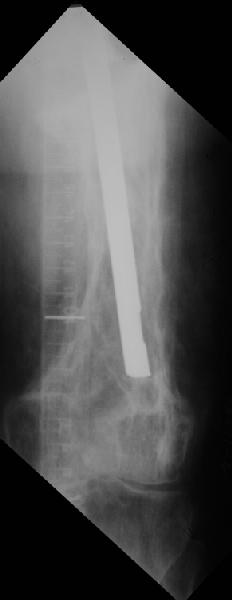

Пациент 82 лет, поступил через 5 мес. с несросшимся переломом после открытого интрамедуллярного остеосинтеза. Выполнили реостеосинтез стержнем 12 мм. ( мах. доступного нам в 2003 г.) Через 4 мес динамизация. В течении 2х лет сращения нет, тем не менее конечность опорна (ходит с тростью). От очередного реостеосинтеза отказались из-за сопутств. патологии.

Еще один пример. Пациентка с юга России, прислала рентгенограммы через год. На сегодня прошло 2 г. 8 мес. после операции. Несмотря на не очень убедительный процесс сращения, пациентка ходит. Учитывая остеопороз при Педжете, решили, что динамизировать вообще не нужно.

При переломах на фоне болезни Педжета металлоконструкция часто служит эндопротезом, несущим нагрузку. Динамизация индивидуальна,- по рентген-динамике. Основной упор- на медикаментозную терапию- см. канд. дисс. Колондаева А.Ф.

Стержень можно было бы поставить подлиннее.